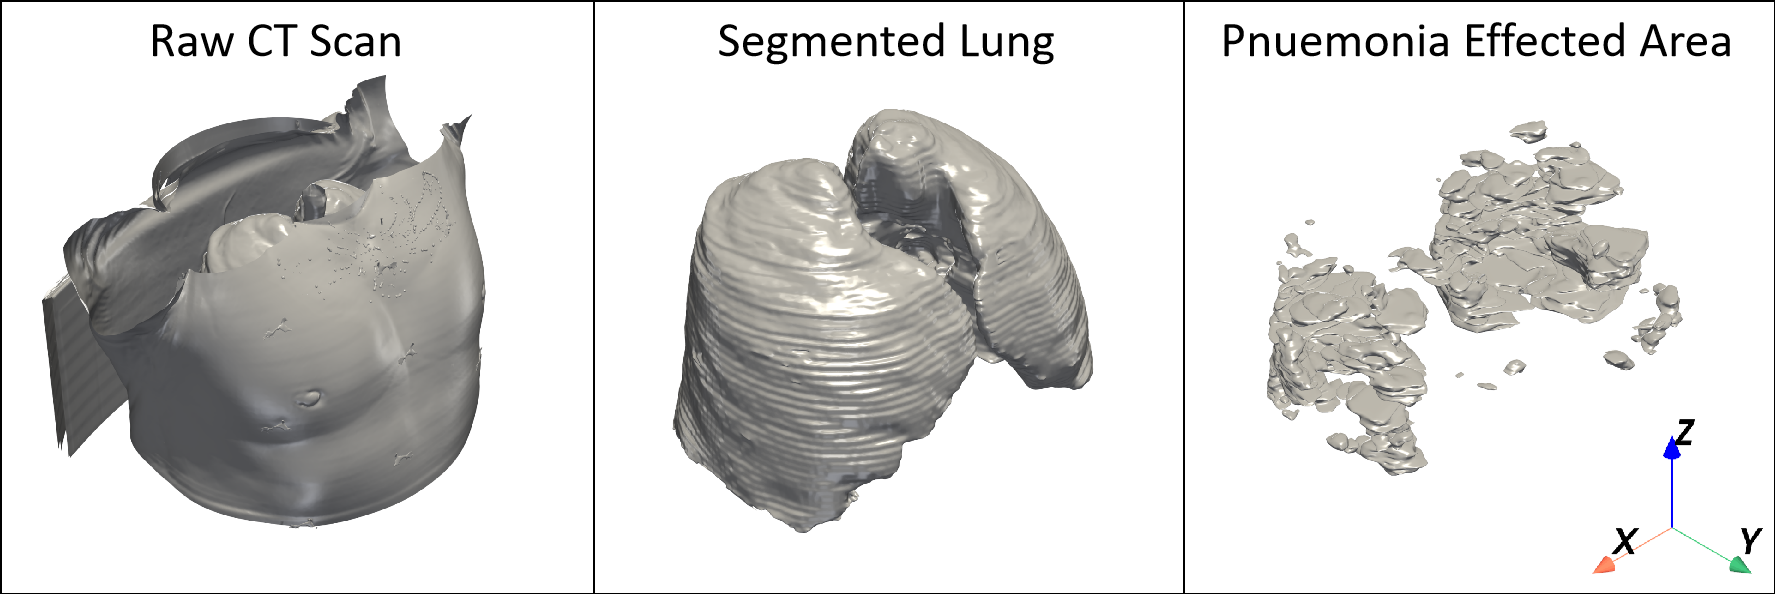

Raw CT scan (left), extracted lung region (middle), and pneumonia-affected regions (right).